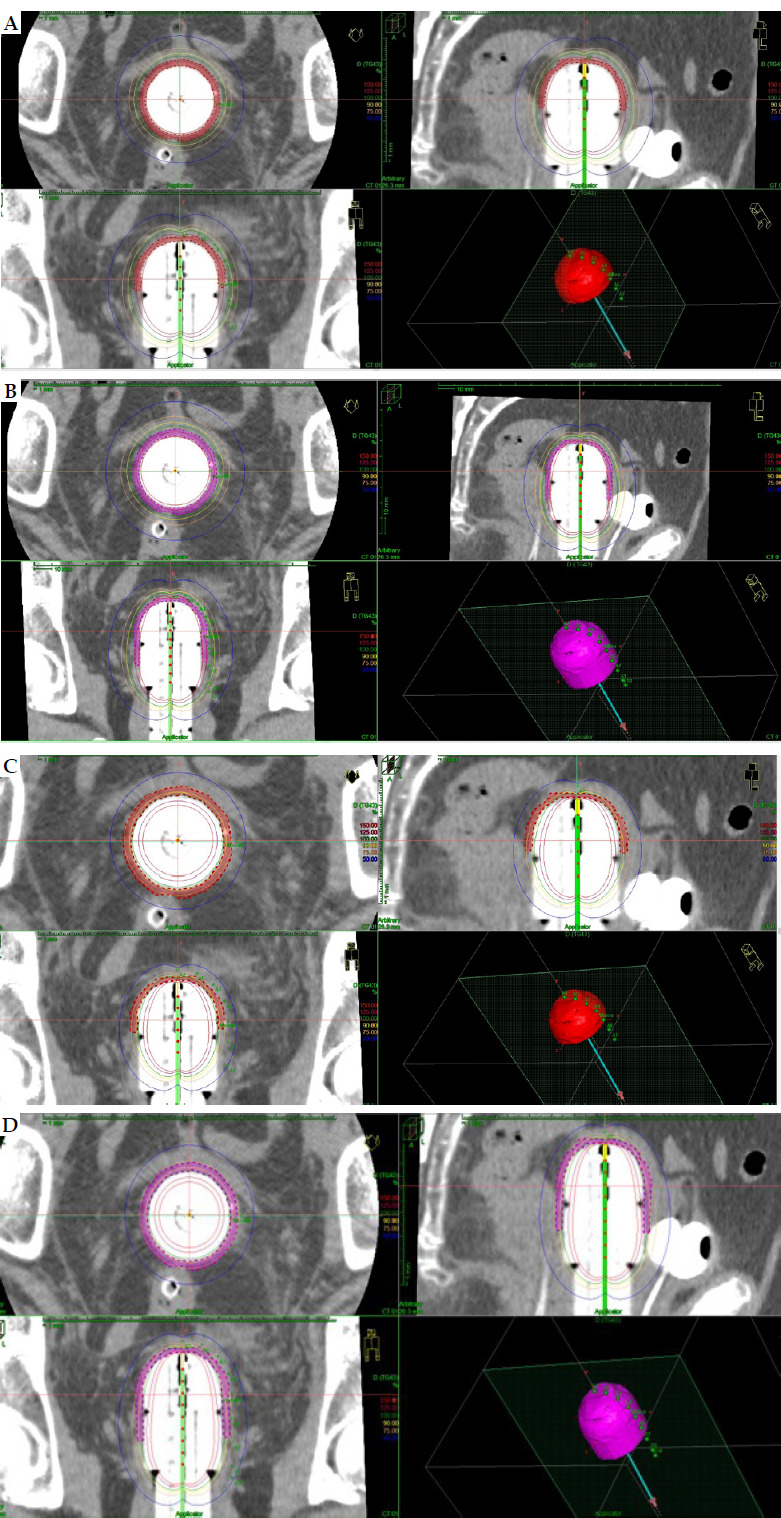

Material and methods: Three different computed tomography (CT) studies for vaginal cylinders of 3.5 cm, 3 cm, and 2.5 cm were performed. Clinical target volume (CTV) was delineated for 3 cm and 4 cm of vaginal length. Twelve schedules were analyzed obtaining overall vaginal surface dose (Gy) (EQD2 α/β = 10 and α/β = 3), overall D90 CTV (α/β = 10) (Gy), and overall D2cc (α/β = 3) for organs at risk (OARs), such as vagina, rectum, sigmoid, rectum, and bladder. Prescription at 5 mm from the applicator surface and at the surface were analyzed for each case.

Results: The overall vaginal surface dose and dose to CTV varied widely among the different schedules, and CTV delineation was necessary in case of surface prescription. The applicator diameter of 3.5 cm showed the best dosimetry results for vaginal surface dose. The overall D2cc OARs' doses changed in the different CT studies.

Abstract Image